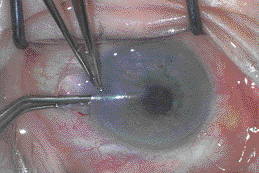

A cystitome-like device is used to inscribe an 8-mm to

9-mm posterior descemetorhexis through the recipient endothelium and

Descemets� membrane. A rake-like irrigating cannula is then used to peel

off and remove Descemets� membrane over the area within the

capsulorrhexis area, leaving behind bare stroma. The posterior stromal-endothelial

lamellar graft is then folded and inserted into the anterior chamber

(Figure 1). The incision is sutured closed and the graft is unfolded by

expanding the anterior chamber with air so that the donor stromal side

lies in apposition to the recipient posterior stroma. Fluid is aspirated

from the donor-host interface through the paracentral corneal vents,

which had been created at the beginning of the procedure. The patient

lies face up for 15 to 60 minutes.

Figure 1. Folded DSEK button being

inserted into anterior chamber through incision.